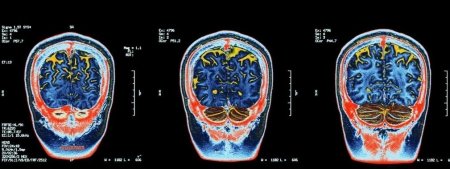

, Neurology, , . , , . 500 000 57 32 000 .

, : , . , , . , . , , ( ).